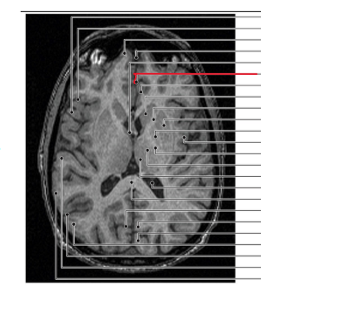

claustrum

putamen

globus pallidus

capsula interna (corona radiata)

capsula externa

capsula extrema

hippocampus

amygdala

fornix